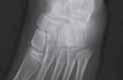

17.3.2.4. Złamania bliższej przynasady piszczeli (złamanie Cozena)

Złamania bliższej przynasady piszczeli występują rzadko (11% złamań piszczeli u dzieci), najczęściej w wieku pomiędzy 3. a 6. rokiem życia. Szczelina złamania ma zwykle przebieg poprzeczny. Często jest to złamanie typu zielonej gałązki. Może mu towarzyszyć złamanie kości strzałkowej lub jej deformacja plastyczna. Nie zdarza się często, ale ma duże znaczenie kliniczne, ponieważ może prowadzić do postępującej koślawej deformacji kończyny. Do złamania dochodzi najczęściej w mechanizmie urazu, którego siła działa od boku na kończynę wyprostowaną w stawie kolanowym.

Rozpoznanie

W badaniu klinicznym dominują ból i obrzęk okolicy bliższej przynasady piszczeli, bolesne ruchy bierne w stawie kolanowym. Może być widoczna deformacja koślawa. Ruchy czynne są zniesione. Należy dokładnie zbadać ukrwienie i unerwienie kończyny z powodu ryzyka wystąpienia zespołu ciasnoty przedziałów powięziowych. Złamanie można sklasyfikować jako poprzeczne, skośne, zielonej gałązki, deformację plastyczną, złamanie typu torus Badanie RTG wykonujemy w pozycji AP i bocznej. Bardzo pomocne może być wykonanie badania TK.